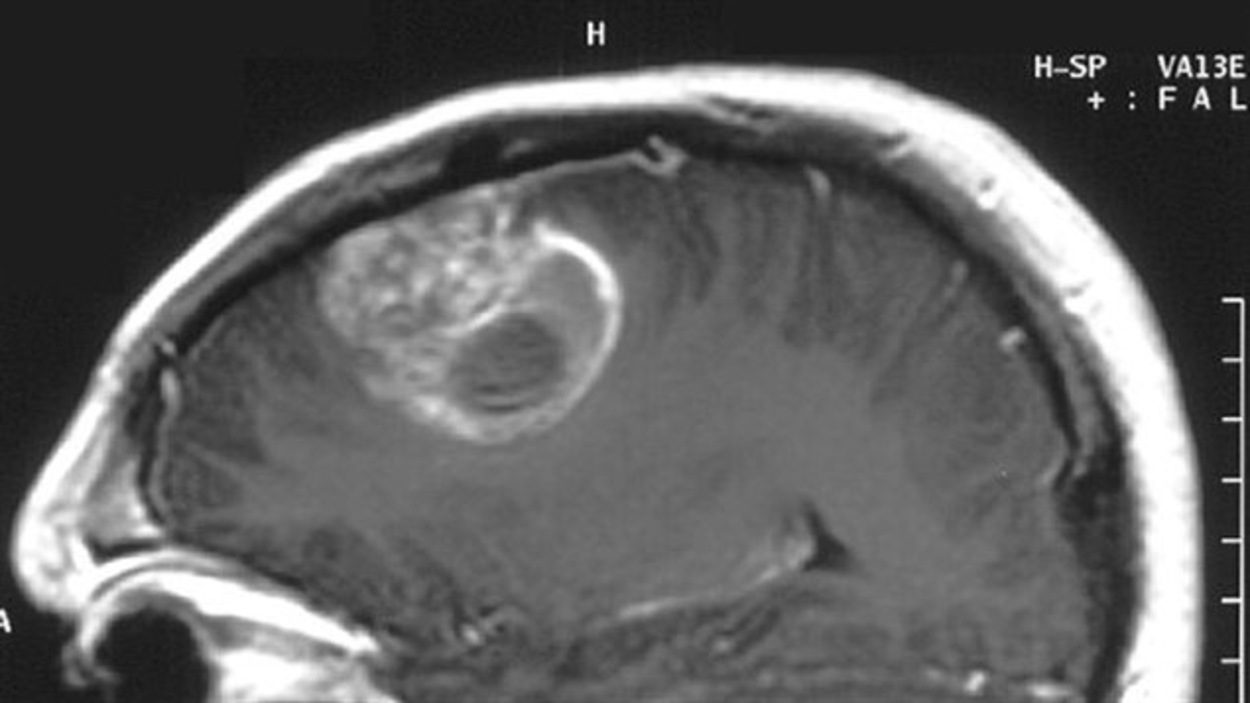

Sep 17, 18 · The exact cause of a benign tumor is often unknown It develops when cells in the body divide and grow at an excessive rate Typically, the body isMay 07, 21 · Get Cancer Uterus Tumeurs ImagesEndometrial cancer (more common) and uterine sarcoma Néanmoins, cet organe peut être atteint de tumeurs cancéreuses, dont on distingue 2 types Cancer of the womb (uterus) is a common cancer of the female reproductive system that often causes abnormal vaginal bleedingSchéma général de la méthode proposée pour la segmentation de tumeurs et de structures internes du cerveau MRI of brain (a) T1weighted image without contrast enhancement

Images de France 169 likes · 1 talking about this Douce France à visiter Mise en page par bastien chevillard luimêmeImage historique d´une tumeur mammaire géante Safaa Ammouri, Anas Saissi Corresponding author Safaa Ammouri, Service de GynécologieObstétrique et Endoscopie Gynécologique Maternité, Faculté de Médecine et Pharmacie, Université Mohammed V, Rabat, Maroc Received 06 Apr Accepted 30 May Published 13 Jul DomainUNet pour lutter contre les tumeurs cérébrales Les tumeurs cérébrales se développent au sein de la boite crânienne Il peut s'agir de métastases, secondaires à un autre cancer développé initialement hors du cerveau (cancer du sein, du poumon, du rein ou de la peau le plus souvent) ou bien de tumeurs cérébrales primitives, issues des cellules présentes normalement dans le

Segmentation 3D de tumeurs et de structures internes du cerveau en IRM Hassan Khotanlou Download PDF Download Full PDF Package This paper A short summary of this paper 37 Full PDFs related to this paper READ PAPER Segmentation 3D de tumeurs et de structures internes du cerveau en IRMFind the perfect Tumeur Cutanée stock photos and editorial news pictures from Getty Images Select from premium Tumeur Cutanée of the highest qualityFind the perfect Tumeur Bénigne stock photos and editorial news pictures from Getty Images Select from premium Tumeur Bénigne of the highest quality